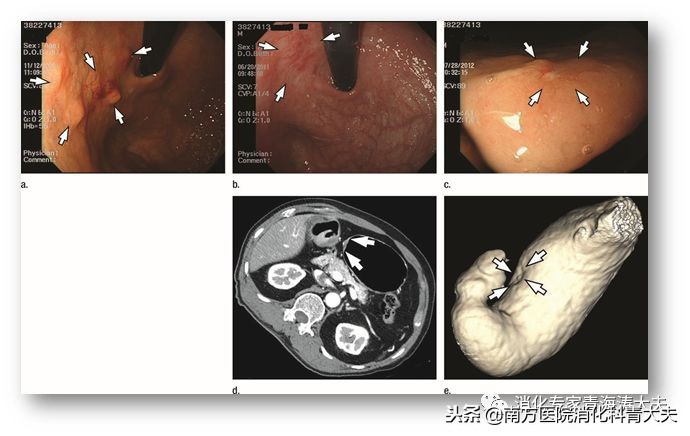

ESD术后同时性异时性癌的内镜特点

研究表明小于1cm的原发肿瘤大小与同时性癌有关,胃下1/3的肿瘤与异时性癌有关。同时性癌更可能较小的原因尚不清楚。然而,考虑到大多数同时多灶性病变位于胃的同一个三分之一处,一些小的多灶性病变随着它们的生长有可能合并成单一的病变。在一项研究中,异时性胃癌倾向于在与原发病灶相同的三分之一的胃中发展,具有类似的大体表现和分化类型。有研究表明多个胃病变患者中超过50%的肿瘤在随访期间在胃的相同纵向位置发展。有趣的是,大多数新发现的病变显示出与原发病变相同的内镜和组织病理学类型。然而,还有其他研究报道,大多数异时性胃腺癌发生在除先前切除部位以外的部位。另外两项研究表明,背景胃粘膜萎缩与异时性胃癌的发展有关。需要更多的研究来明确异时性癌发生部位与原发灶的关系。有研究发现原发病灶的未分化组织学表现与同时或异时性胃癌的发生有关。非隆起型病变、无同时性癌是早期出现异时性癌的危险因素,可能与初次检查漏诊微小癌或癌前病变有关。